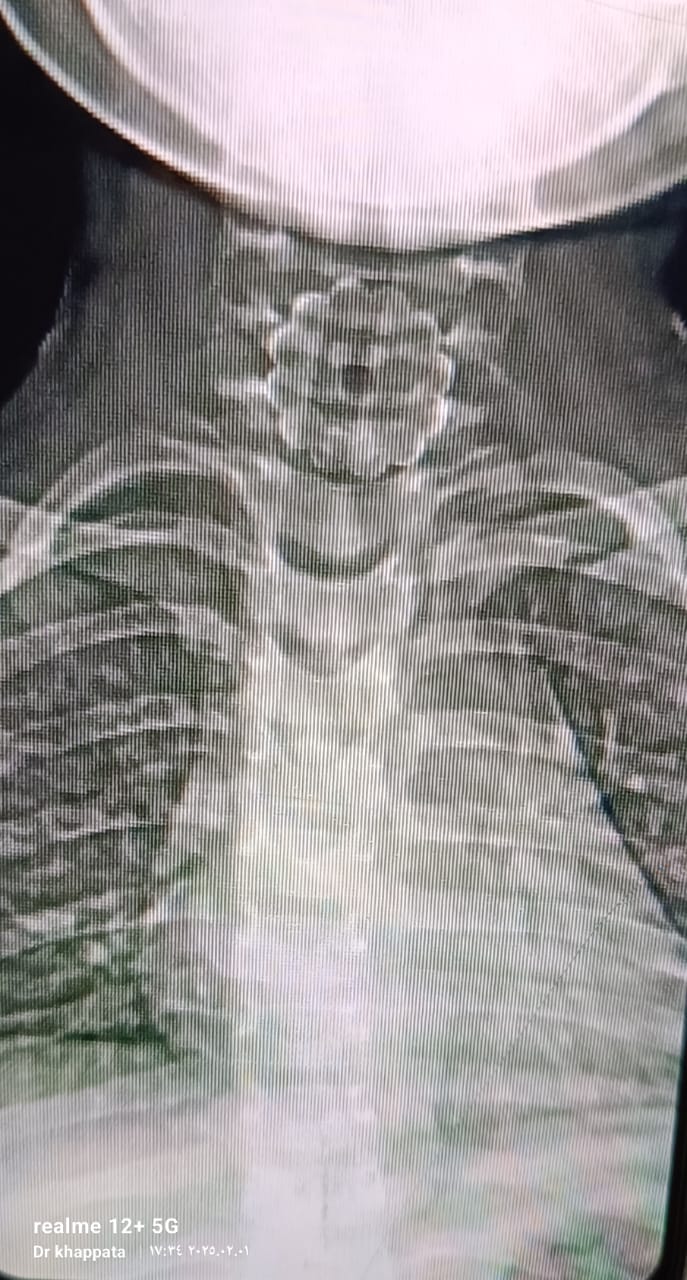

تمكن أطباء كلية الطب بجامعة الأزهر خلال القافلة الشاملة التى تنظمها الجامعة بمدن حلايب وشلاتين من إنقاذ طفلة ابتلعت جسم غريب زرار عباية خلال عملهم بمستشفى الشلاتين المركزى.

وأشارت منسق القافلة شام على إلى أنه تم ابلاغ القافلة من قسم الطوارئ بحاله اختناق لطفله ٥ سنوات بسبب بلع جسم غريب ( زرار عبايه).

وعلى الفور تم توجه فريق طبى يضم طبيب جراحه الانف والاذن والحنجره وطبيب جراحه الاطفال وطبيب التخدير، وتم تحضير غرفه العمليات وادخال الحاله على الفور وتم استخراج الجسم الغريب تحت المخدر العام وتم خروج الحاله بسلام.